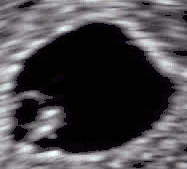

In obstetrics, heart rate can be measured by ultrasonography, such as in this embryo (at bottom left in the sac) of 6 weeks with a heart rate of approximately 90 per minute.

A more precise method of determining heart rate involves the use of an electrocardiograph, or ECG (also abbreviated EKG). An ECG generates a pattern based on electrical activity of the heart, which closely follows heart function. Continuous ECG monitoring is routinely done in many clinical settings, especially in critical care medicine. On the ECG, instantaneous heart rate is calculated using the R wave-to-R wave (RR) interval and multiplying/dividing in order to derive heart rate in heartbeats/min. Multiple methods exist: